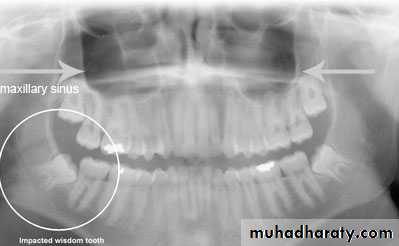

1- clinical inspection to disclose the missing tooth2- radiographic assessment showing the position of the unerupted tooth

3- standard radiographic technique used to localize the unerupted tooth and these will include

b – periapical and occlusal filmc – panoramic view (OPG)

Classification of impacted upper third molar

1- pell and Gregory according to the relation of the impacted tooth to the occlusal plane of the upper second molar2- the relation of the impacted upper third molar to the maxillary sinus

Relation of the impacted maxillary third molar to the maxillary sinus

Class A sinus approximation ( less than 2 mm bone between the antrum and the impacted tooth )Class B non sinus approximation ( more than 2 mm of bone exist between the impacted tooth and the sinus )